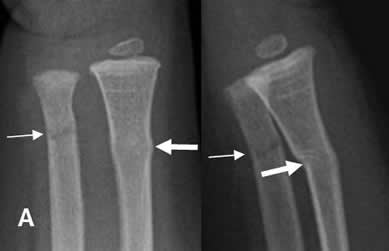

Fig 64. Fractura en leño verde.

A: Rx AP y B: Rx lateral. Fractura en leño verde del cúbito distal. (Flechas delgadas). Adicionalmente hay fractura en torus del radio distal. (Flecha gruesa).